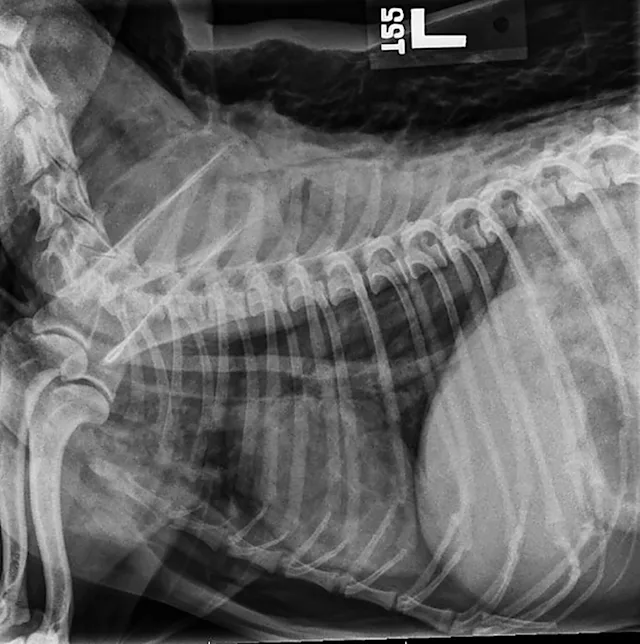

Lateral x-ray showing abnormally detailed views of intrathoracic structures and radiolucency between body wall and skin.

A pneumomediastinum diagnosis is made via thoracic radiography (Figures 1 and 2). Air in the mediastinum outlines the cranial vena cava, dorsal and ventral tracheal walls, esophagus, and aorta. Gas may be present in the retroperitoneal space, cervical fascial planes, and subcutaneous space.2 If an obvious cause of pneumomediastinum is not apparent and the patient is stable, an oropharyngeal examination may be performed with the patient under sedation. Fluoroscopy with iodinated water-soluble contrast or endoscopy can be used to evaluate for esophageal lesions. Airway integrity may be assessed via endoscopy, although small lesions in the trachea may be missed. Advanced imaging (eg, CT) can be helpful in identifying the underlying lesion.